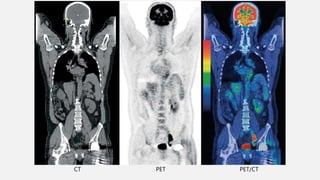

DIAGNÓSTICO

CT PET PET/CT